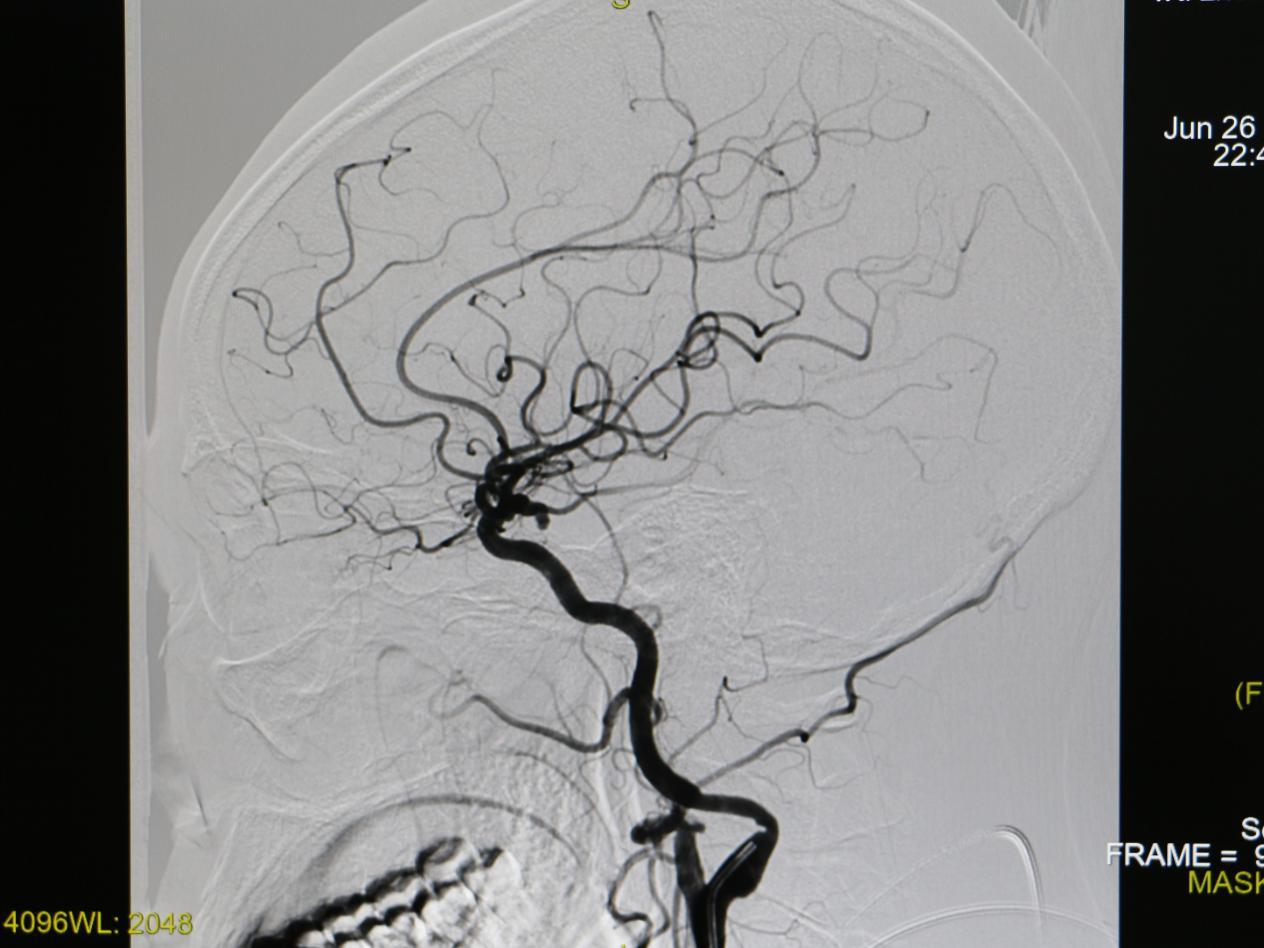

6月26日,该院行首例经脑动脉插管全脑动脉造影术

脑血管多发动脉瘤

2.jpg

脑血管多发动脉瘤(3D图像)